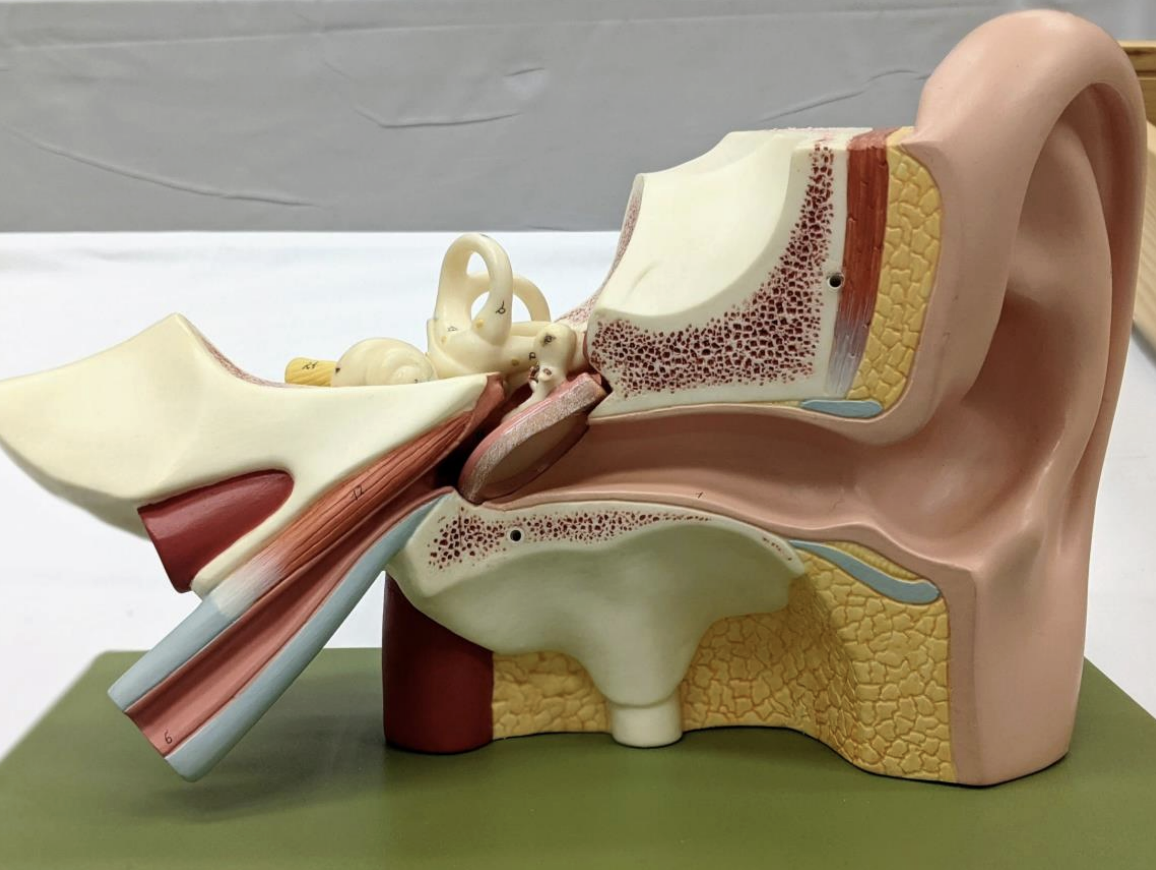

The Middle Ear

External auditory canal

Tympanic membrane

Malleus & Incus

Horizontal semicircular canals

Vestibule

Vestibulocochlear nerve

Tensor tympani

Pharyngotympanic tube